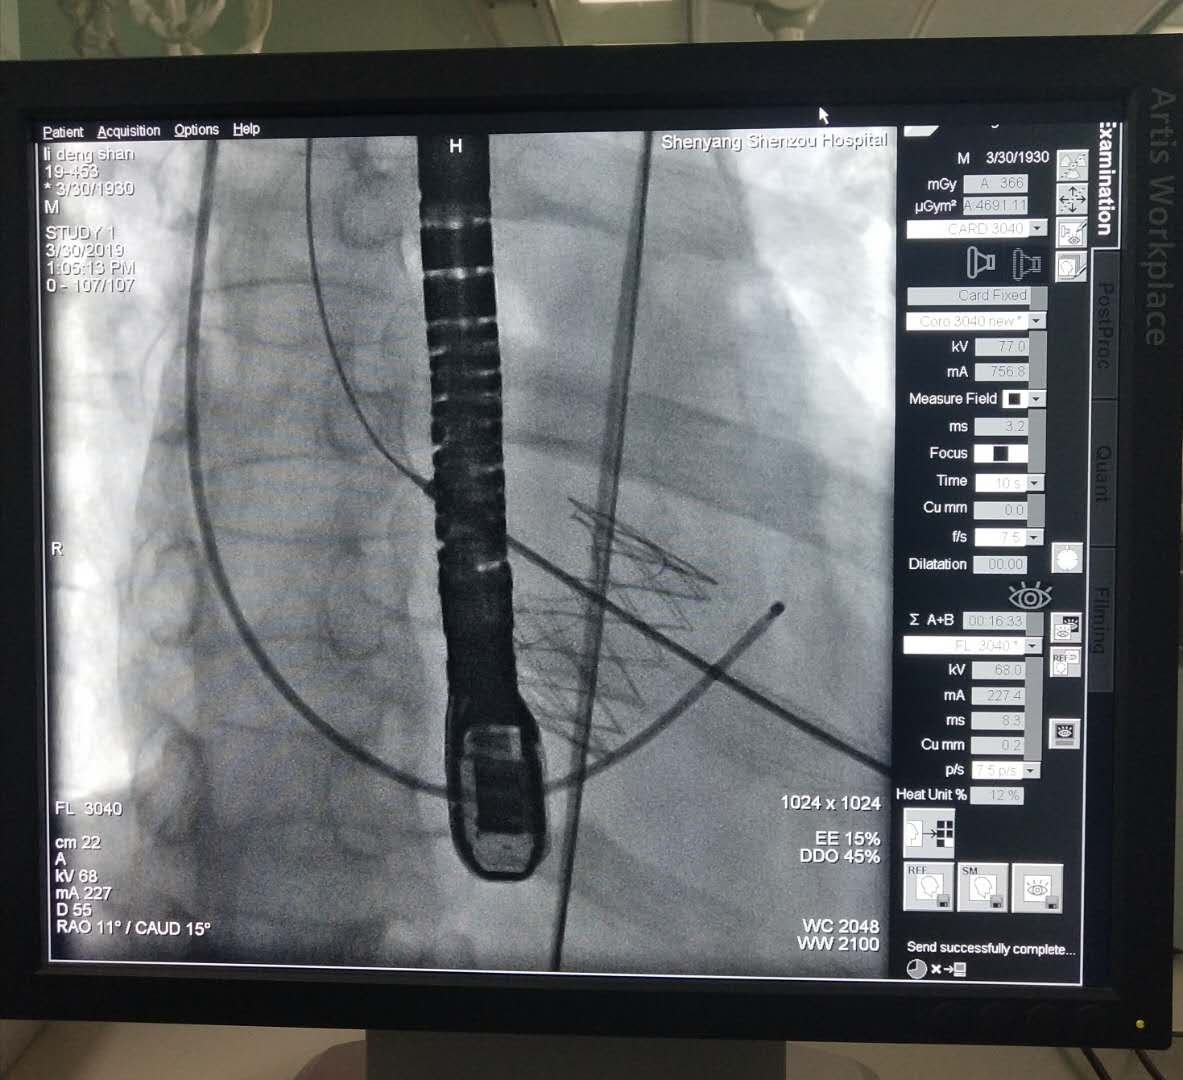

11点手术正式开始, 全麻后,经左侧第五肋间小切口5cm依次经胸,显露心尖,双荷包缝合,穿刺心尖并置管,主动脉根部造影,示:主动脉瓣重度关闭不全,根据术前CT和超声心动图测量的主动脉瓣环直径,选用29mm的J-Valve介入人工心脏瓣膜,植入原主动脉瓣环处。

再次造影及TEE发现:主动脉瓣无返流,介入瓣膜形态满意,无瓣周漏,无跨瓣压差。

DSA下人工心脏瓣膜释放与固定